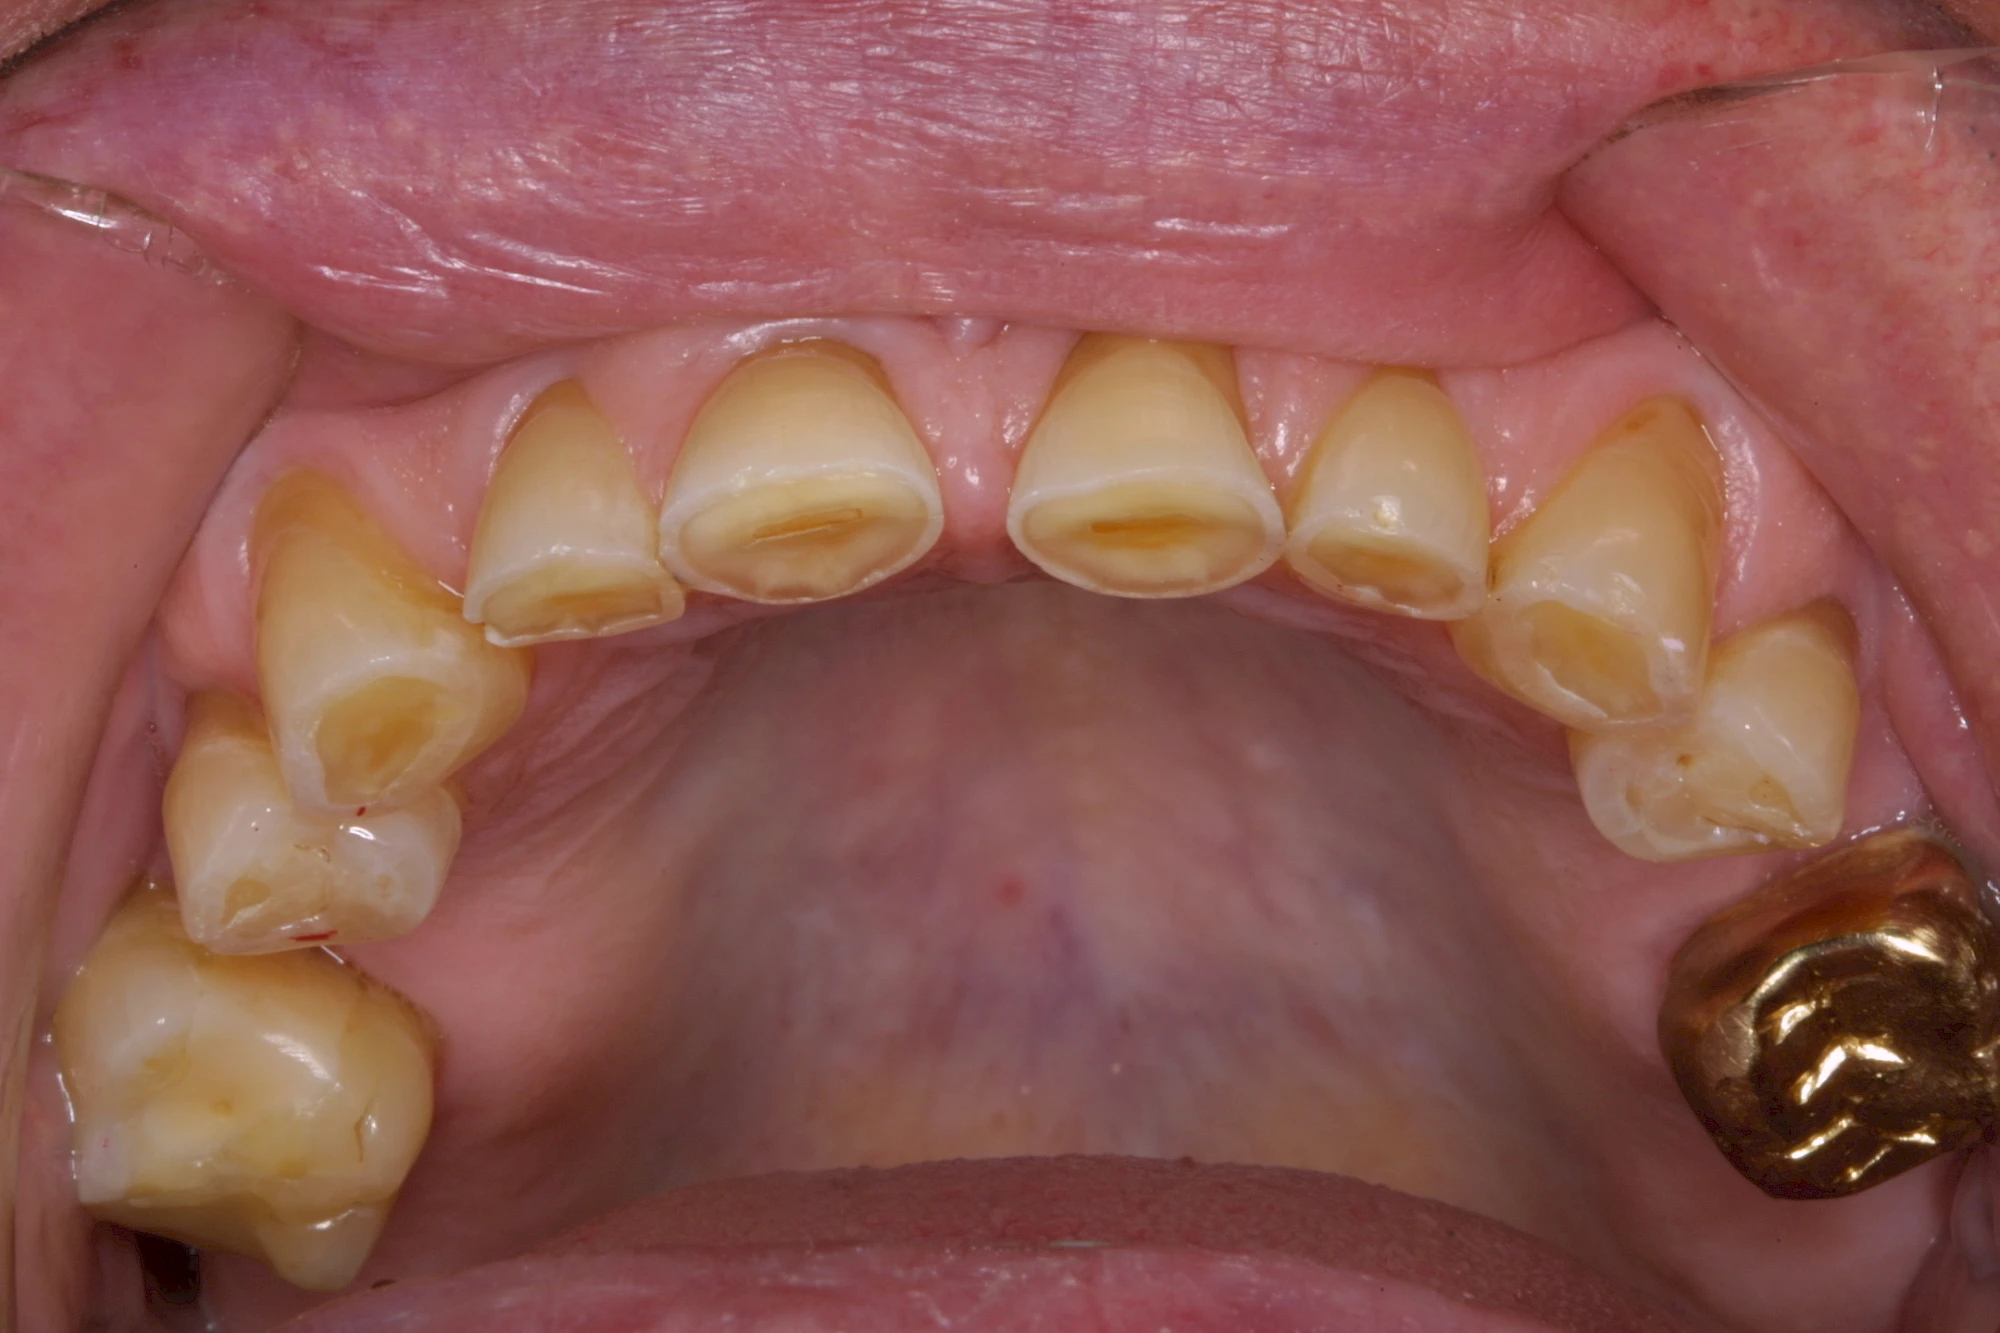

Auswaschung (Erosion) dagegen ist eine Verschleißerscheinung der Zähne aufgrund von immer wiederkehrenden Säureangriffen durch die Nahrung, verstärkt zum Beispiel durch den Genuss säurehaltiger Getränke oder Speisen. Auch bei Menschen mit einer Essstörung (z. B. Bulimie) können die Zähne durch die Magensäure ausgewaschen erscheinen.